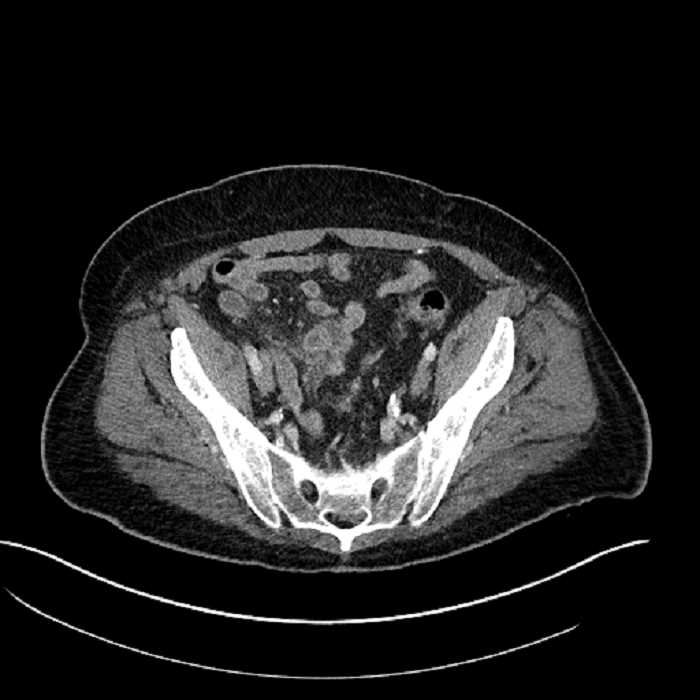

Age: 63

Sex: Male

Indication: Abdominal pain

• Large fluid density structure in hepatic segments 7 and 8 measuring 10 x 7 x 7 cm with internal septation and circumferential ill-defined low density compatible with edema

• Peripherally enhancing subcapsular collections along the anterior margin of the left hepatic lobe measuring 3 x 1 cm and 2 x 1 cm

• Clearly marginated fluid density structure in segment 7 and several other scattered tiny hypodensities, which likely represent cysts

• Mild mural thickening of a segment of the sigmoid colon with adjacent fat stranding and a 1.5 cm fluid and gas collection along the tip of an inflamed diverticulum

• Loss of the normal fat plane between this collection and adjacent loops of small bowel, which demonstrate mural thickening

• High grade stenosis of the left common iliac artery, with the left internal and external iliac arteries remaining patent

• Ankylosis of both sacroiliac joints

Acute sigmoid diverticulitis complicated by a small contained perforation and a large abscess in the right hepatic lobe. Additional small subcapsular abscesses along the anterior margin of the left hepatic lobe.

Additionally, loss of the normal fat plane between the peridiverticular collection and adjacent thickened loops of small bowel raises the potential for an enterocolonic fistula.

High grade stenosis of the left common iliac artery. The left external and internal iliac arteries are patent.

Hepatic abscess showing the double target sign with low density internally surrounded by a thin inner enhancing rim (red arrow) and ill-defined outer low density rim (yellow arrow). Blue arrow indicates an internal septation. Red arrows: additional smaller subcapsular abscesses. Red arrow: focal contained perforation associated with diverticulitis.